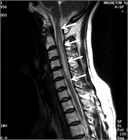

1. 視神経脊髄炎スペクトラム障害(Neuromyelitis optica spectrum disorders:NMOSD)の視神経炎(アクアポリン(AQP)4抗体陽性視神経炎)の再発抑制には生物製剤(ラブリズマブ、エクリズマブ、イネビリズマブ、サトラリズマブ、リツキシマブ)が有効

1. MRIのSTIR法は、視神経炎の病態把握に有用で推奨される(推奨度1)

1. 視神経炎の活動性炎症の有無はMRIのT1強調画像脂肪抑制造影で判断する(推奨度1)